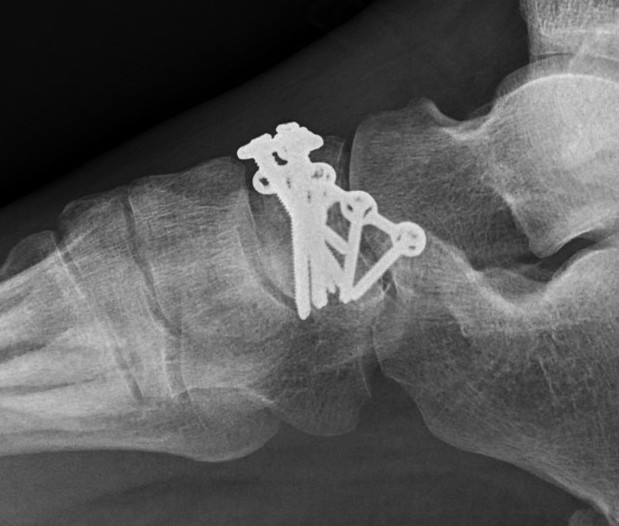

Operative management

Indications

Displacement

Goal

Imperative to maintain medial column length

Options

Screw

Dorsal locking plate

Bridging medial plate - talus to 1st metatarsal

Temporary external fixation

Primary fusion

Acute traumatic fracture treated with navicular plate

AO foundation medial bridge plate technique